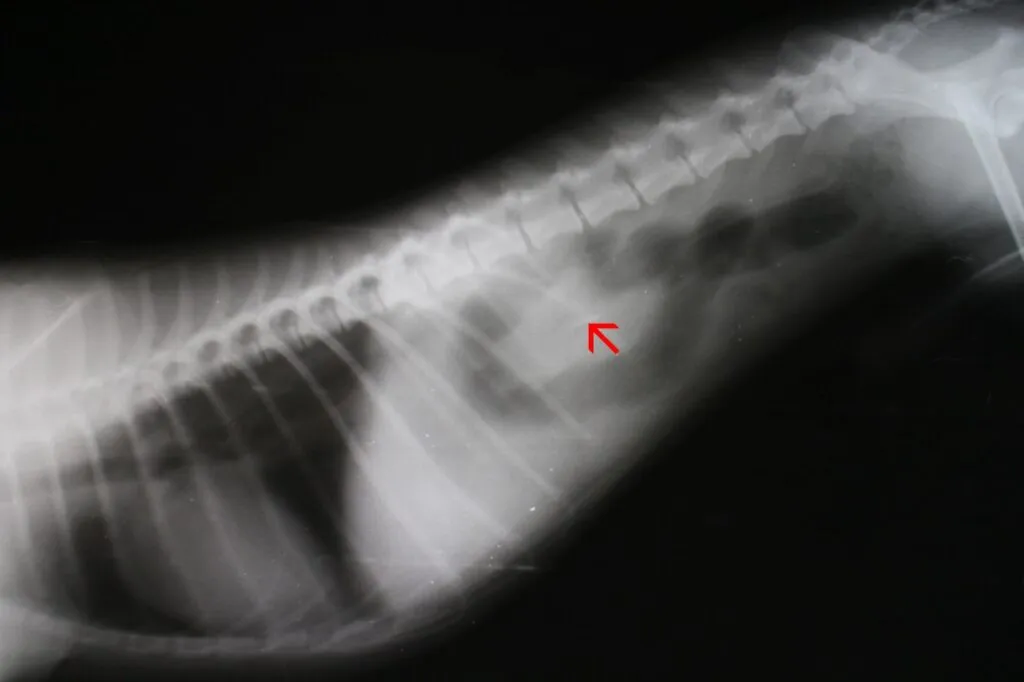

Diagnóstico: como é que o veterinário identifca uma obstrução intestinal num cão?

Chegados ao veterinário, é o estado atual do cão que orienta as medidas a tomar. Portanto, se o animal estiver inconsciente ou em risco de choque, o veterinário tem que tomar medidas de emergência. Se não for esse o caso, pode fazer a avaliação do patudo. Para tal, durante a entrevista clínica com o dono, avalia sinais vitais importantes como a frequência cardíaca e o estado das mucosas.

Exames de imagiologia, como ecografia ou radiografia com contraste, também podem ajudar o veterinário a identificar a causa da obstrução intestinal do cão. Pois todos os dados obtidos são necessários para o melhor planeamento dos procedimentos cirúrgicos em questão.